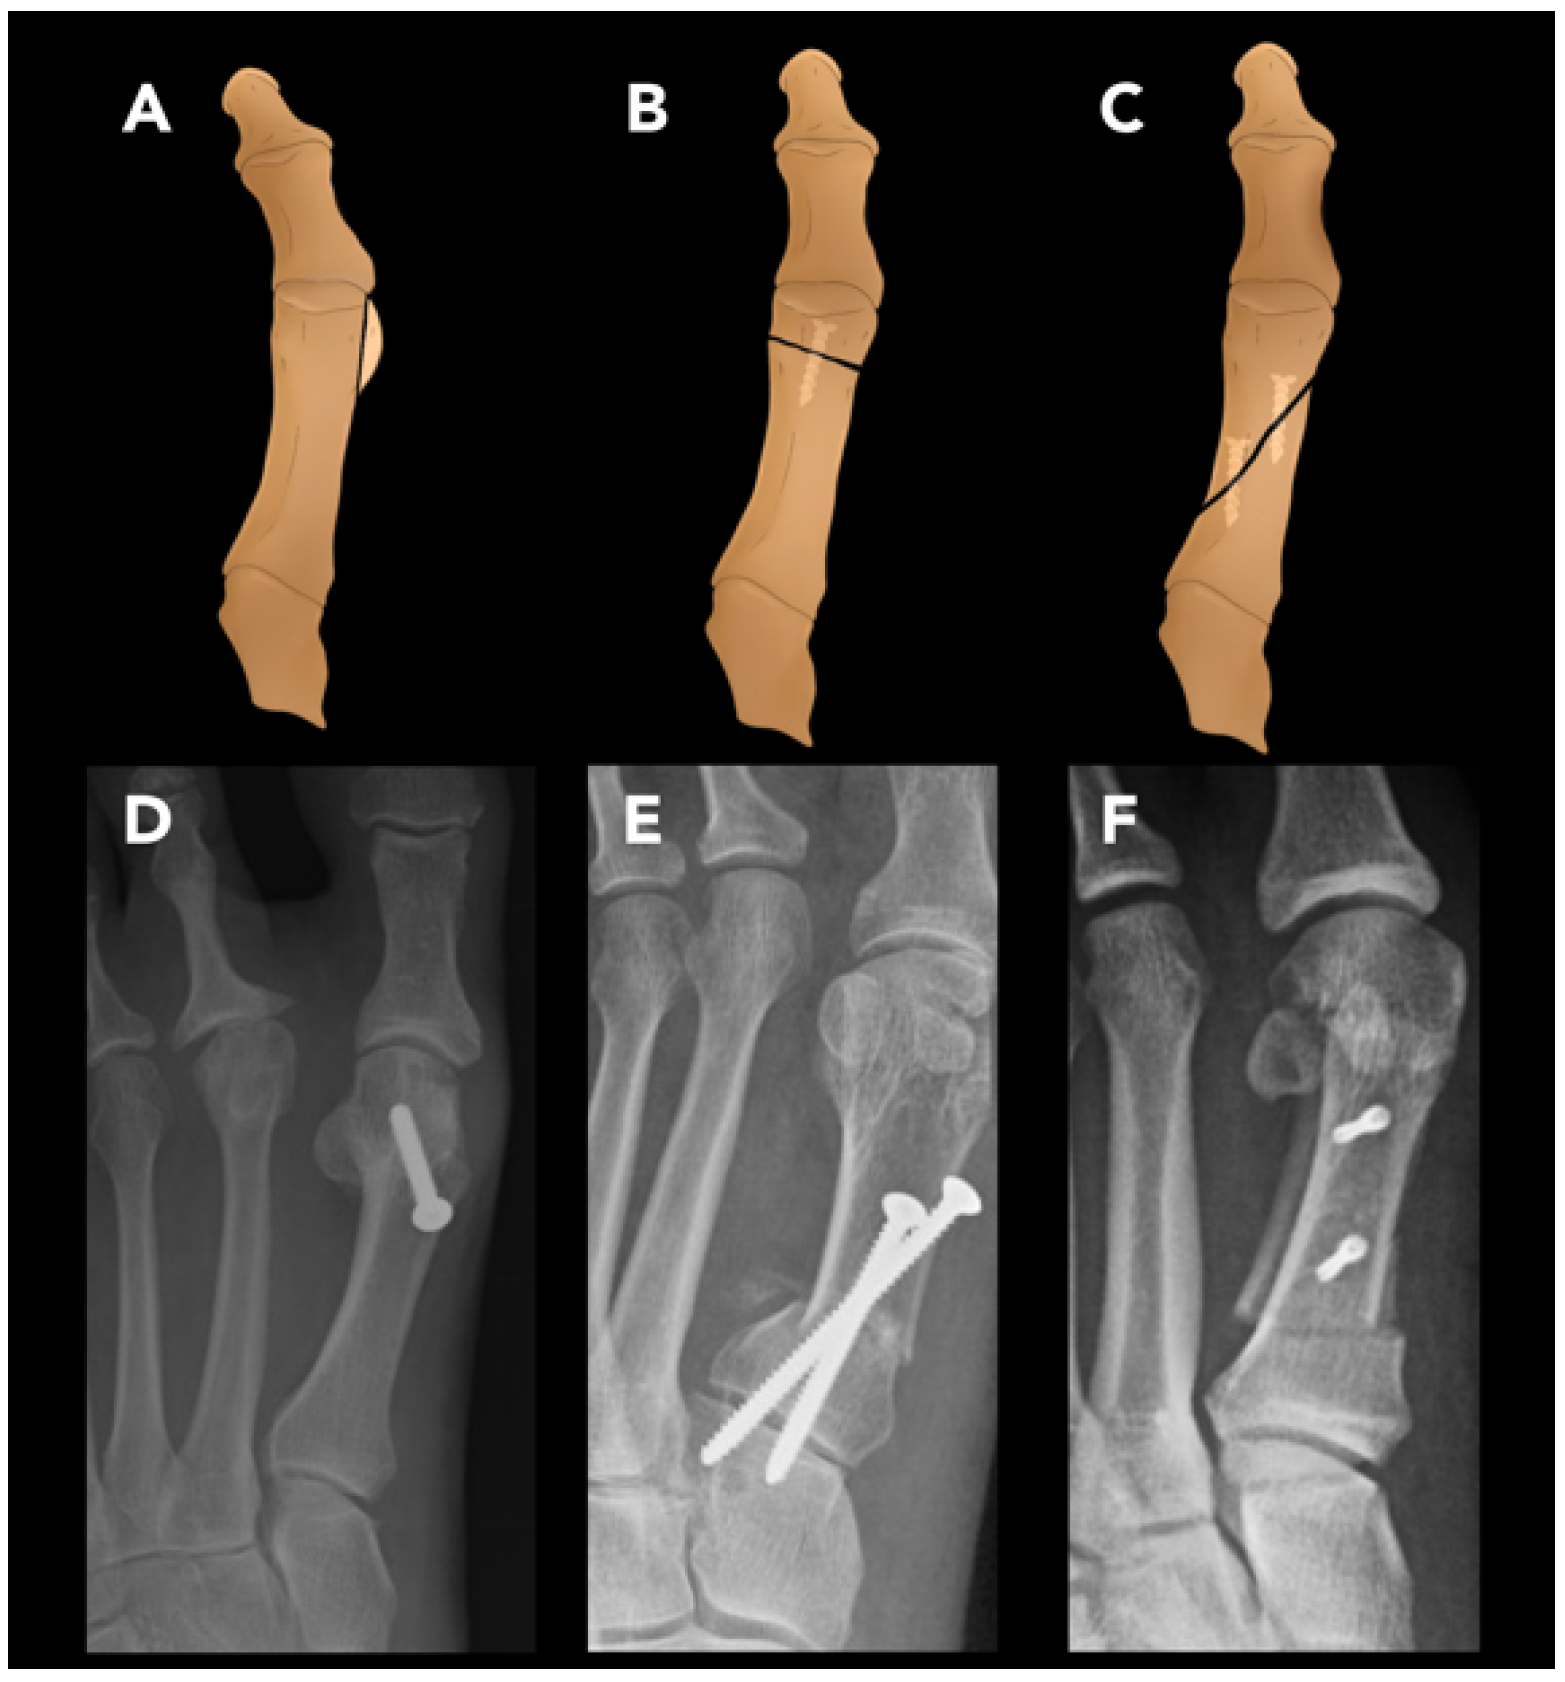

2.3.4. Hallux Valgus Osteotomy